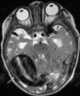

Fetal arteriovenous fistula